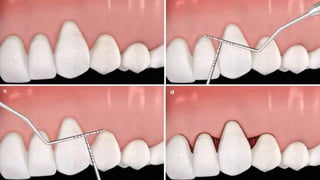

• #9 Coronally advanced flap without vertical releasing incisions. Defects (a), For procedures not involving releasing incisions , the intrasulculary incision should be extended to one to two teeth adjacent of the recession to allow advancement of the flap over the exposed root surface without tension. determination of the papillary incisions (b, c), papillae de-epithelialized (d)

• #10 flap coronally advanced and sutured

• #19 The recipient site is de-epithelialized. In the donor site (i.e. adjacent tooth), a horizontal sub marginal incision is made at the mesial end of the gingival recession and extended in the mesial-distal direction. vertical releasing incision should be made at the end of the horizontal incision and extended to the alveolar mucosa. It is important to highlight that the interdental papilla distal to the defect should be preserved as much as possible.

• #20 a full- or partial-thickness flap (depending on the type of LPF-based technique used) is raised with blade dissection, and a 3-mm-wide collar of intact gingiva should be left undisturbed around the donor tooth. the exposed root surface should be thoroughly, but carefully, planned with hand curettes and/or finishing burs. At this stage, root modification agents may be used, but no additional clinical benefits should be expected. The planned root surface is rinsed with saline; the flap is laterally positioned at the level or beyond (coronal) of the cementoenamel junction and sutured. It is also essential to note that the flap should be passively adapted over the recipient site (i.e. it must remain stable at that position even without sutures), so all muscle inserts located on the internal side of the flap should be removed leaving the flap with no tension. Subsequently, a non-eugenol periodontal dressing may be placed over the donor sites. The dressing and sutures are removed 14 days after surgery. In addition, patients should be instructed not to brush the tooth in the treated area, as well as they are prescribed 0.12 % chlorhexidine gluconate and instructed to rinse gently twice a day for 2–3 weeks or until safe and comfortable tooth brushing can be performed. analgesics, anti-inflammatory drugs and/or systemic antibiotics are prescribed if needed, as well as no adverse effects are expected in the donor or recipient sites.